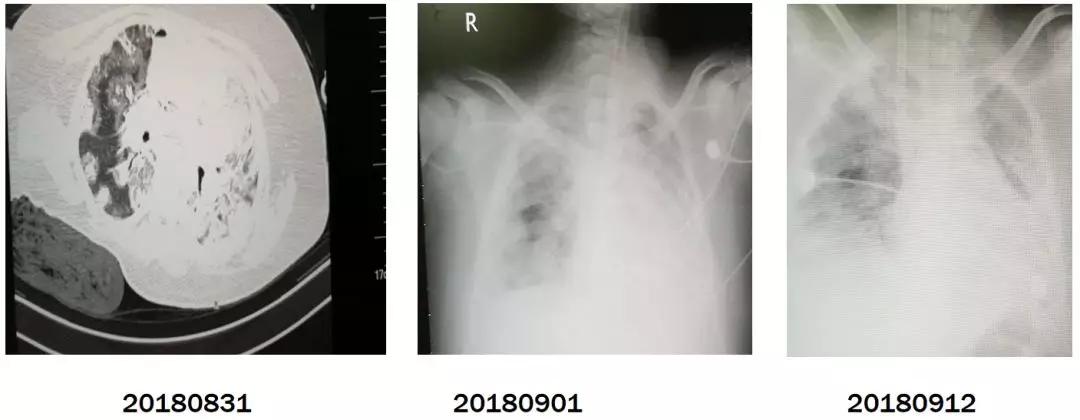

鼻病毒和疱疹病毒共感染一例

男性,14岁,「反复发热、咳嗽、咳痰20天」为主诉入院,平常身体很好。

现病史:20余天前无明显诱因出现发热,体温38.3℃,伴有咳嗽,咳少量白色泡沫痰,遂于当地医院就诊,予退热对症处理(具体不详)后体温可降至正常,但仍有咳嗽,之后发热症状反复出现,体温波动在37-38.5℃之间,遂于另一家医院就诊,查白细胞及中性粒细胞升高。可能是从鼻病毒开始,因为正常体内也有单疱病毒,但在免疫力低下的时候才会致病。胸部CT提示双肺肺炎,予抗感染(具体不详)后效果不佳,气促较前明显,遂于2018-8-28转入ICU治疗,予无创呼吸机辅助通气、抗感染(哌拉西林舒巴坦+万古霉素+莫西沙星+克拉霉素)、激素(甲强龙40mg/d)等治疗后效果仍不佳,发热较前加重,最高体温39.2℃,伴有明显气促,外周血氧86%。

病原学检查:细菌:G-杆菌、鲍曼不动杆菌,真菌:白色假丝酵母菌,病毒:鼻病毒、单纯疱疹病毒。

影像学检查:主要表现:双肺弥漫性间质性病变。

这个病人病情严重,后来由于发现病毒的时候重视病毒感染的治疗,最终病人好转,康复出院。